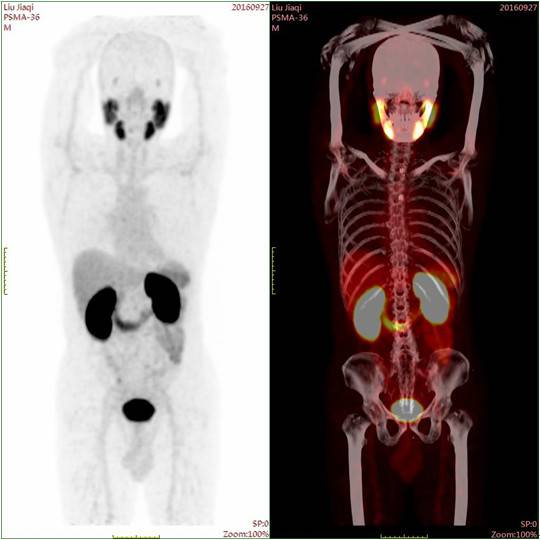

● 评估——PSMA-PET/CT全身扫描

创新技术:新型PSMA PET/CT是近期在国际上最新出现的前列腺癌精准评估技术。技术基础为通过核素标记PSMA(前列腺特异膜抗原),从而显示相关病灶,是目前诊断前列腺癌转移最为敏感的手段,其敏感性远超传统的骨扫描。该技术不仅能观察到骨骼的转移,还能显示远处的软组织转移灶。

这例患者通过PSMA PET/CT扫描显示肿瘤仅局限在前列腺内,未见盆腔淋巴结及其它部位转移。因此治疗方案定为前列腺根治性切除术,不需进行盆腔淋巴结清扫。